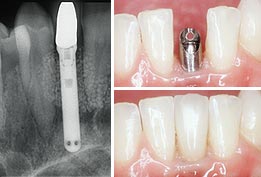

Anterior Replacement

Anterior replacement is used to replace the incisors or cuspids, also known as your front teeth.